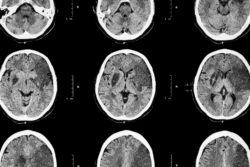

Xarelto stroke brain ct scanA Kentucky woman says she suffered a stroke and GI bleeding after taking Xarelto.

The stroke and GI bleeding lawsuit alleges that Connie suffered from a gastrointestinal bleed on Nov. 8, 2016 and a stroke a few days later. She says she suffered from “life-threatening, irreversible bleeding from the use of Xarelto, as well as severe pain and suffering.”